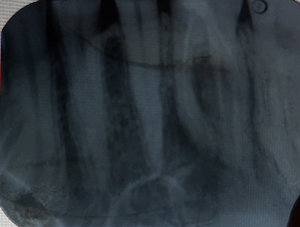

После удаления нерва из зуба, кажется четырнадцатый, на верхней челюсти, проткнули на 2 сантиметра дальше корня, я показался другому врачу и он говорит, что теперь нужно удалять зуб.

Неужели ничего нельзя поделать, чтобы сохранить зуб? Чем-то запломбировать этот канал? Мне 66 лет, их, зубов, уже почти не осталось.

В принципе, доктор прав, также возможно провести хирургическую манипуляцию (резекция верхушки корня).